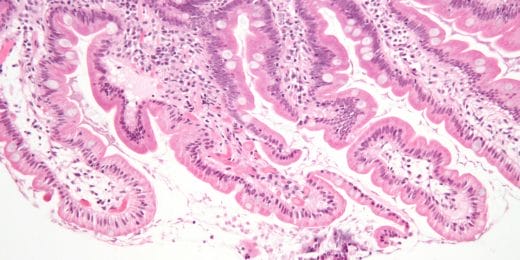

Enteritis

Ontsteking van de dunne darm. Deze wordt zelden alleen ...